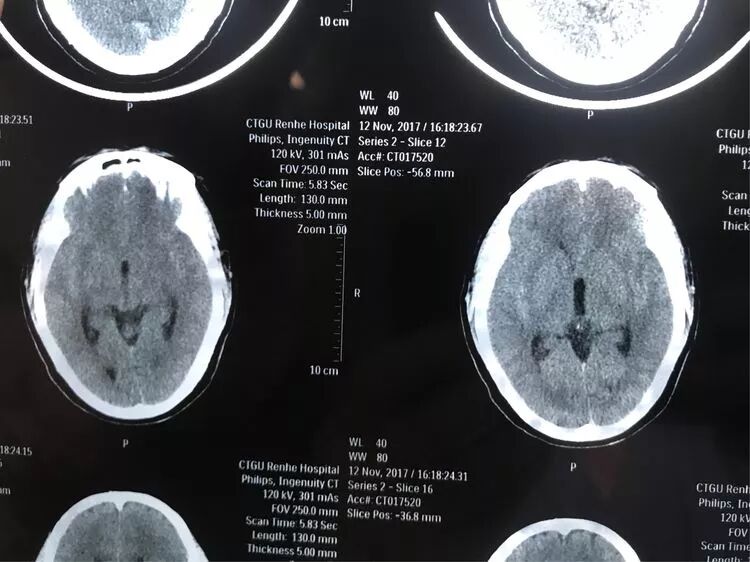

女,73岁,蛛网膜下腔出血量还挺多的,H-H 分级4级

造影显示左侧后交通动脉瘤

椎动脉造影没发现大脑后动脉,双侧的大脑后动脉都是由颈内动脉-后交通动脉发出,双侧胚胎型大脑后动脉